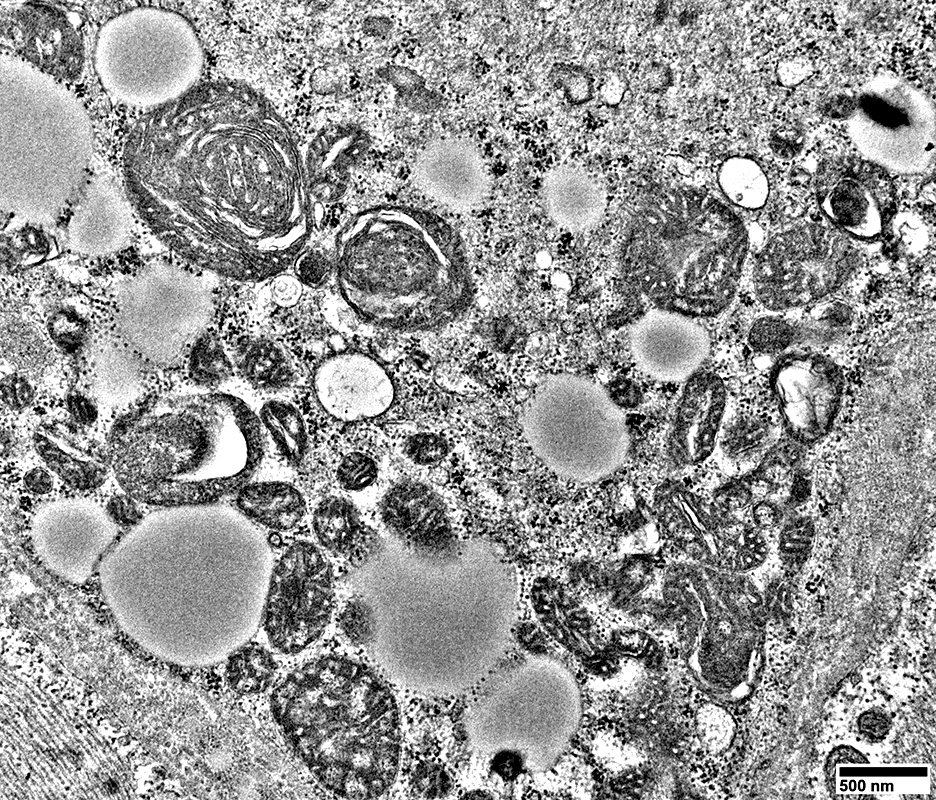

MELAS: Mitochondrial Ultrastructure

From: R Schmidt